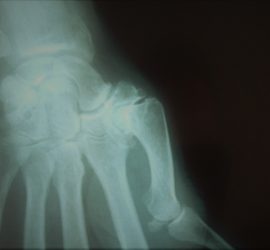

Rizartrose

Rizartrose   O que é a rizartrose? Rizartrose é o nome dado à artrose da base do polegar. A artrose é caraterizada, entre outras alterações, por um desgaste da cartilagem articular e formação de osteófitos (os vulgares bicos de papagaio). A base do polegar é composta por várias articulações, das […]